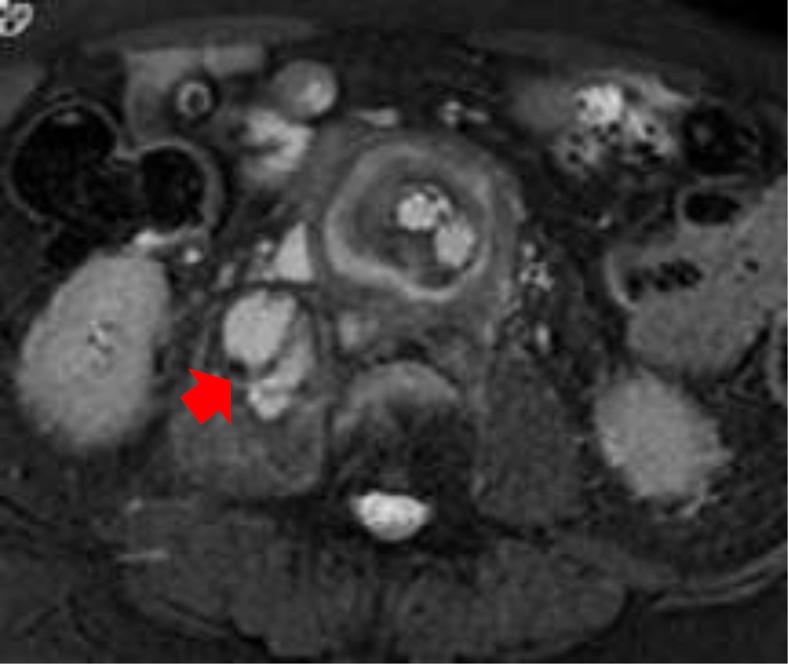

We report the case of an 82-year-old patient with an infected abdominal aortic endograft who presented with a right psoas abscess and lumbar osteomyelitis. The psoas abscess was drained percutaneously. Fluid obtained grew The patient, an active and highly functional individual, wished to pursue definitive management. The infected endograft was surgically removed, and the aorta was ligated above the renal arteries after staged axillary-bifemoral, hepatorenal, and splenorenal bypasses.

我们报告了一例82岁感染性腹主动脉内移植物患者,该患者出现右腰大肌脓肿和腰椎骨髓炎。经皮引流了腰大肌脓肿。引流获得的液体培养出……该患者积极且功能良好,希望进行确定性治疗。手术切除了感染的内移植物,并在分期进行腋-双股、肝-肾和脾-肾旁路手术后,在肾动脉上方结扎了主动脉。